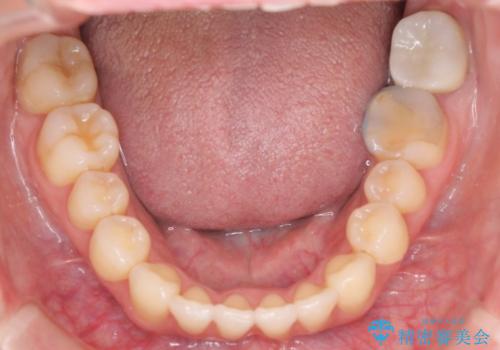

- 出っ歯で口が閉じずらくて、前歯でものかが噛み切れないとのことで来院されました。

上顎の前歯が前方に傾斜して、下顎の前歯と接触していない状態でした。

上顎の前から4番目の歯を両側抜歯して前歯を後方に移動させる計画としました。

前歯がしっかり下がることで、上下の前歯があわさり食事もしやすくなったと言っていただきました。